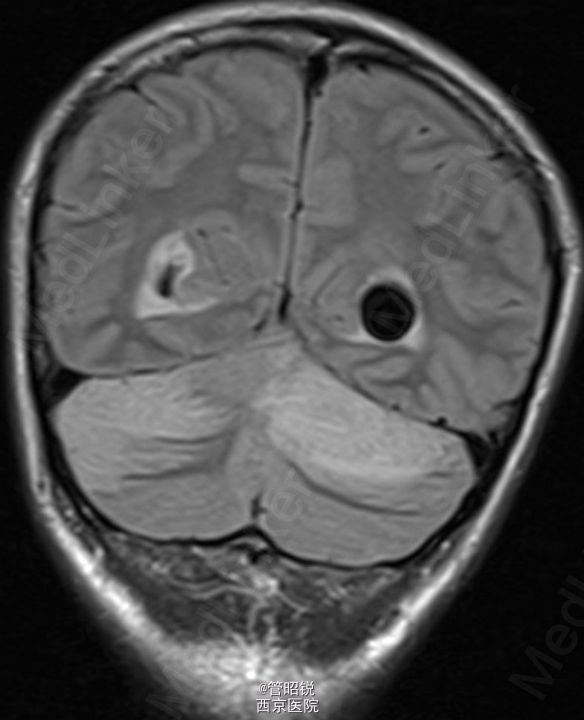

患者,男,29岁,头痛、颈痛2周 入院时CT正常,24小时后 T2WI (B) 和 T2W-FLAIR (C)显示高信号增强,脑水肿,沟回消失。CE-T1WI (D)显示脑膜线样增强。随后12小时的非增强CT显示小脑水肿压迫脑干,由于阻塞性脑积水使颞角膨大,需要紧急行颅后窝颅骨切除减压术。(影像资料比较典型。和大家分享下 AJNR-case of the week)

诊断:急性小脑炎 治疗上应早期应用激素治疗,水肿严重时应手术行颅骨减压。

急性小脑炎是以小脑功能损害为主的炎性综合症。发病前期一般有感染病史,多见于儿童。临床表现多样,主要有躯干和肢体的共济失调,发热,眼球运动异常,言语不清,头痛,恶心、呕吐和意识水平的下降。临床诊断主要依据其典型的影像学检查,临床表现和脑脊液检查结果。